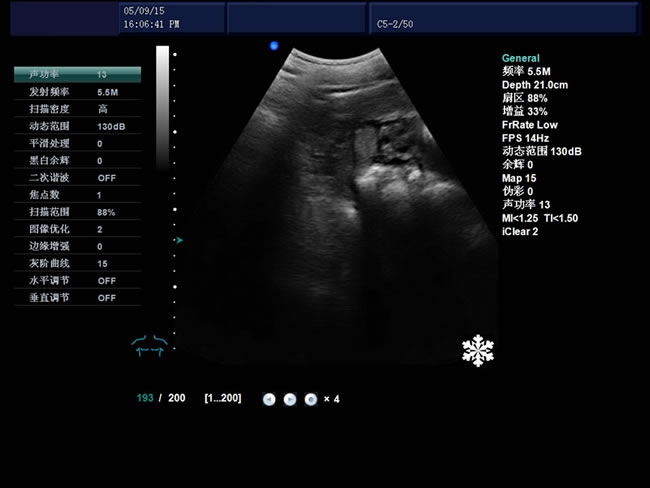

• S8彩色多普勒獸用超聲診斷儀是徐州市大為電子設(shè)備有限公司推出的一款全新的彩色超聲診斷儀器。

適用范圍:B超機(jī)產(chǎn)品性能

高集成數(shù)字式彩色多普勒技術(shù)

寬頻探頭,頻率范圍從2.0MHz到10.0MHz

1、檢查母豬的空懷,降低無效飼養(yǎng)的功效早已深入人心

2、用B超監(jiān)測可及早準(zhǔn)確掌握妊娠母豬頭數(shù),較高的早期妊娠診斷準(zhǔn)確率較好的保證了均衡生產(chǎn)

3、探查時(shí)間短、無應(yīng)激、準(zhǔn)確率高,而且產(chǎn)生巨大的生產(chǎn)應(yīng)用價(jià)值